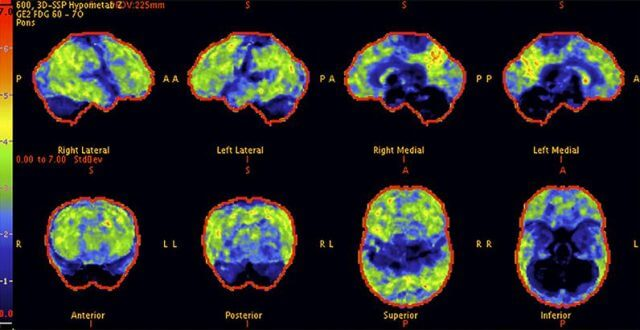

Above: The patient’s PET scan after AlzClipp treatment shows improvement, with cognitive abilities greatly enhanced as the scan approaches that of a normal brain.

Above: A 68-year-old woman with a 10-year history of cognitive issues. Previous PET scans showed significant metabolic decline, indicating Alzheimer’s.